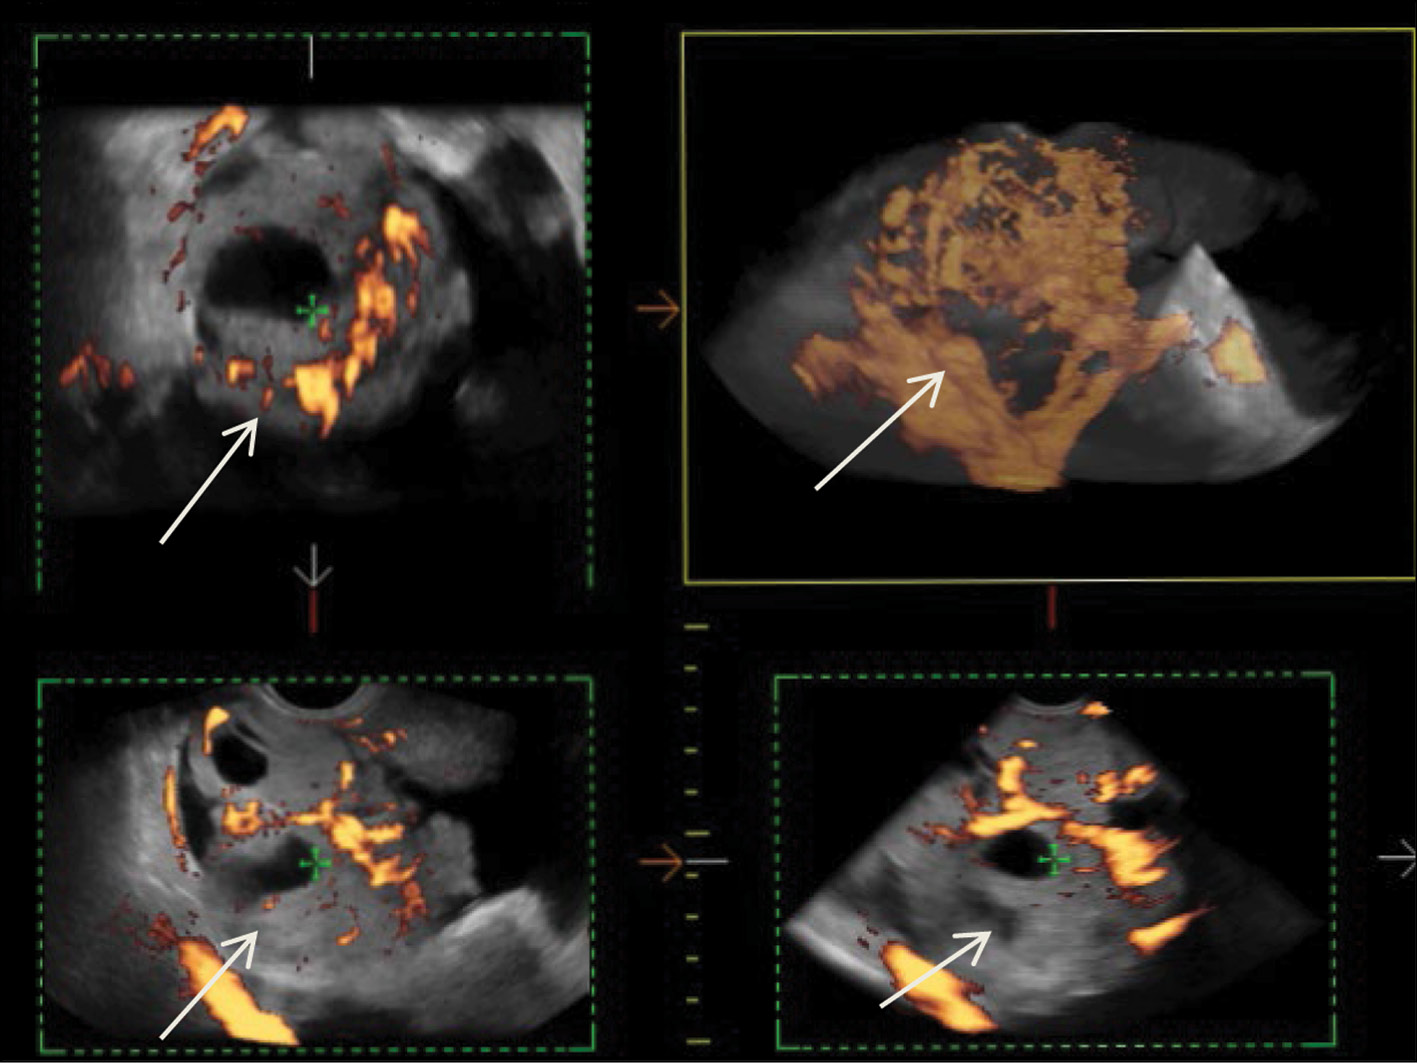

Malignant struma of the right ovary was detected 2 years after surgical treatment of primary benign struma of the left ovary. Six months later, the patient was diagnosed with a disease relapse, visualized exclusively according to radioisotope research methods. In the fourth year of anticancer treatment, ultrasonography revealed recurring foci along the peritoneum. According to the ultrasound data on the pelvic peritoneum and the projection of the removed right ovary, multiple solid nodes with high blood flow were visualized. Peak systolic velocity ranged from 2 to 9 cm/s in minor lesions from 4 to 12 mm, with an RI max of 0.53. For 4 years, the patient underwent radioiodine therapy with 131I with an activity of 6.0 GBq; the patient’s condition during the treatment was satisfactory.